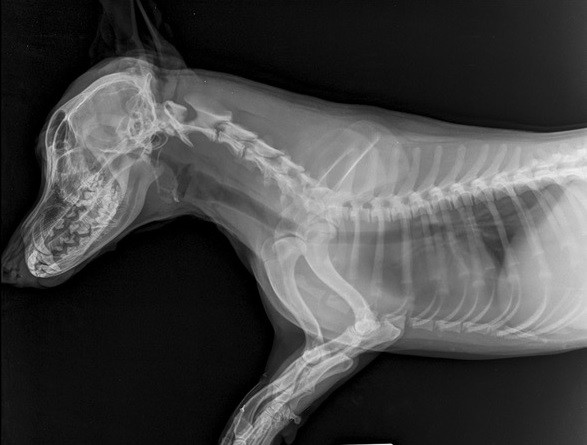

Akútny abdomen z pohľadu zobrazovacích procedúr (2x45min) |

Bolestivý krk nie je vždy len Woblerov syndróm (2x45min) |